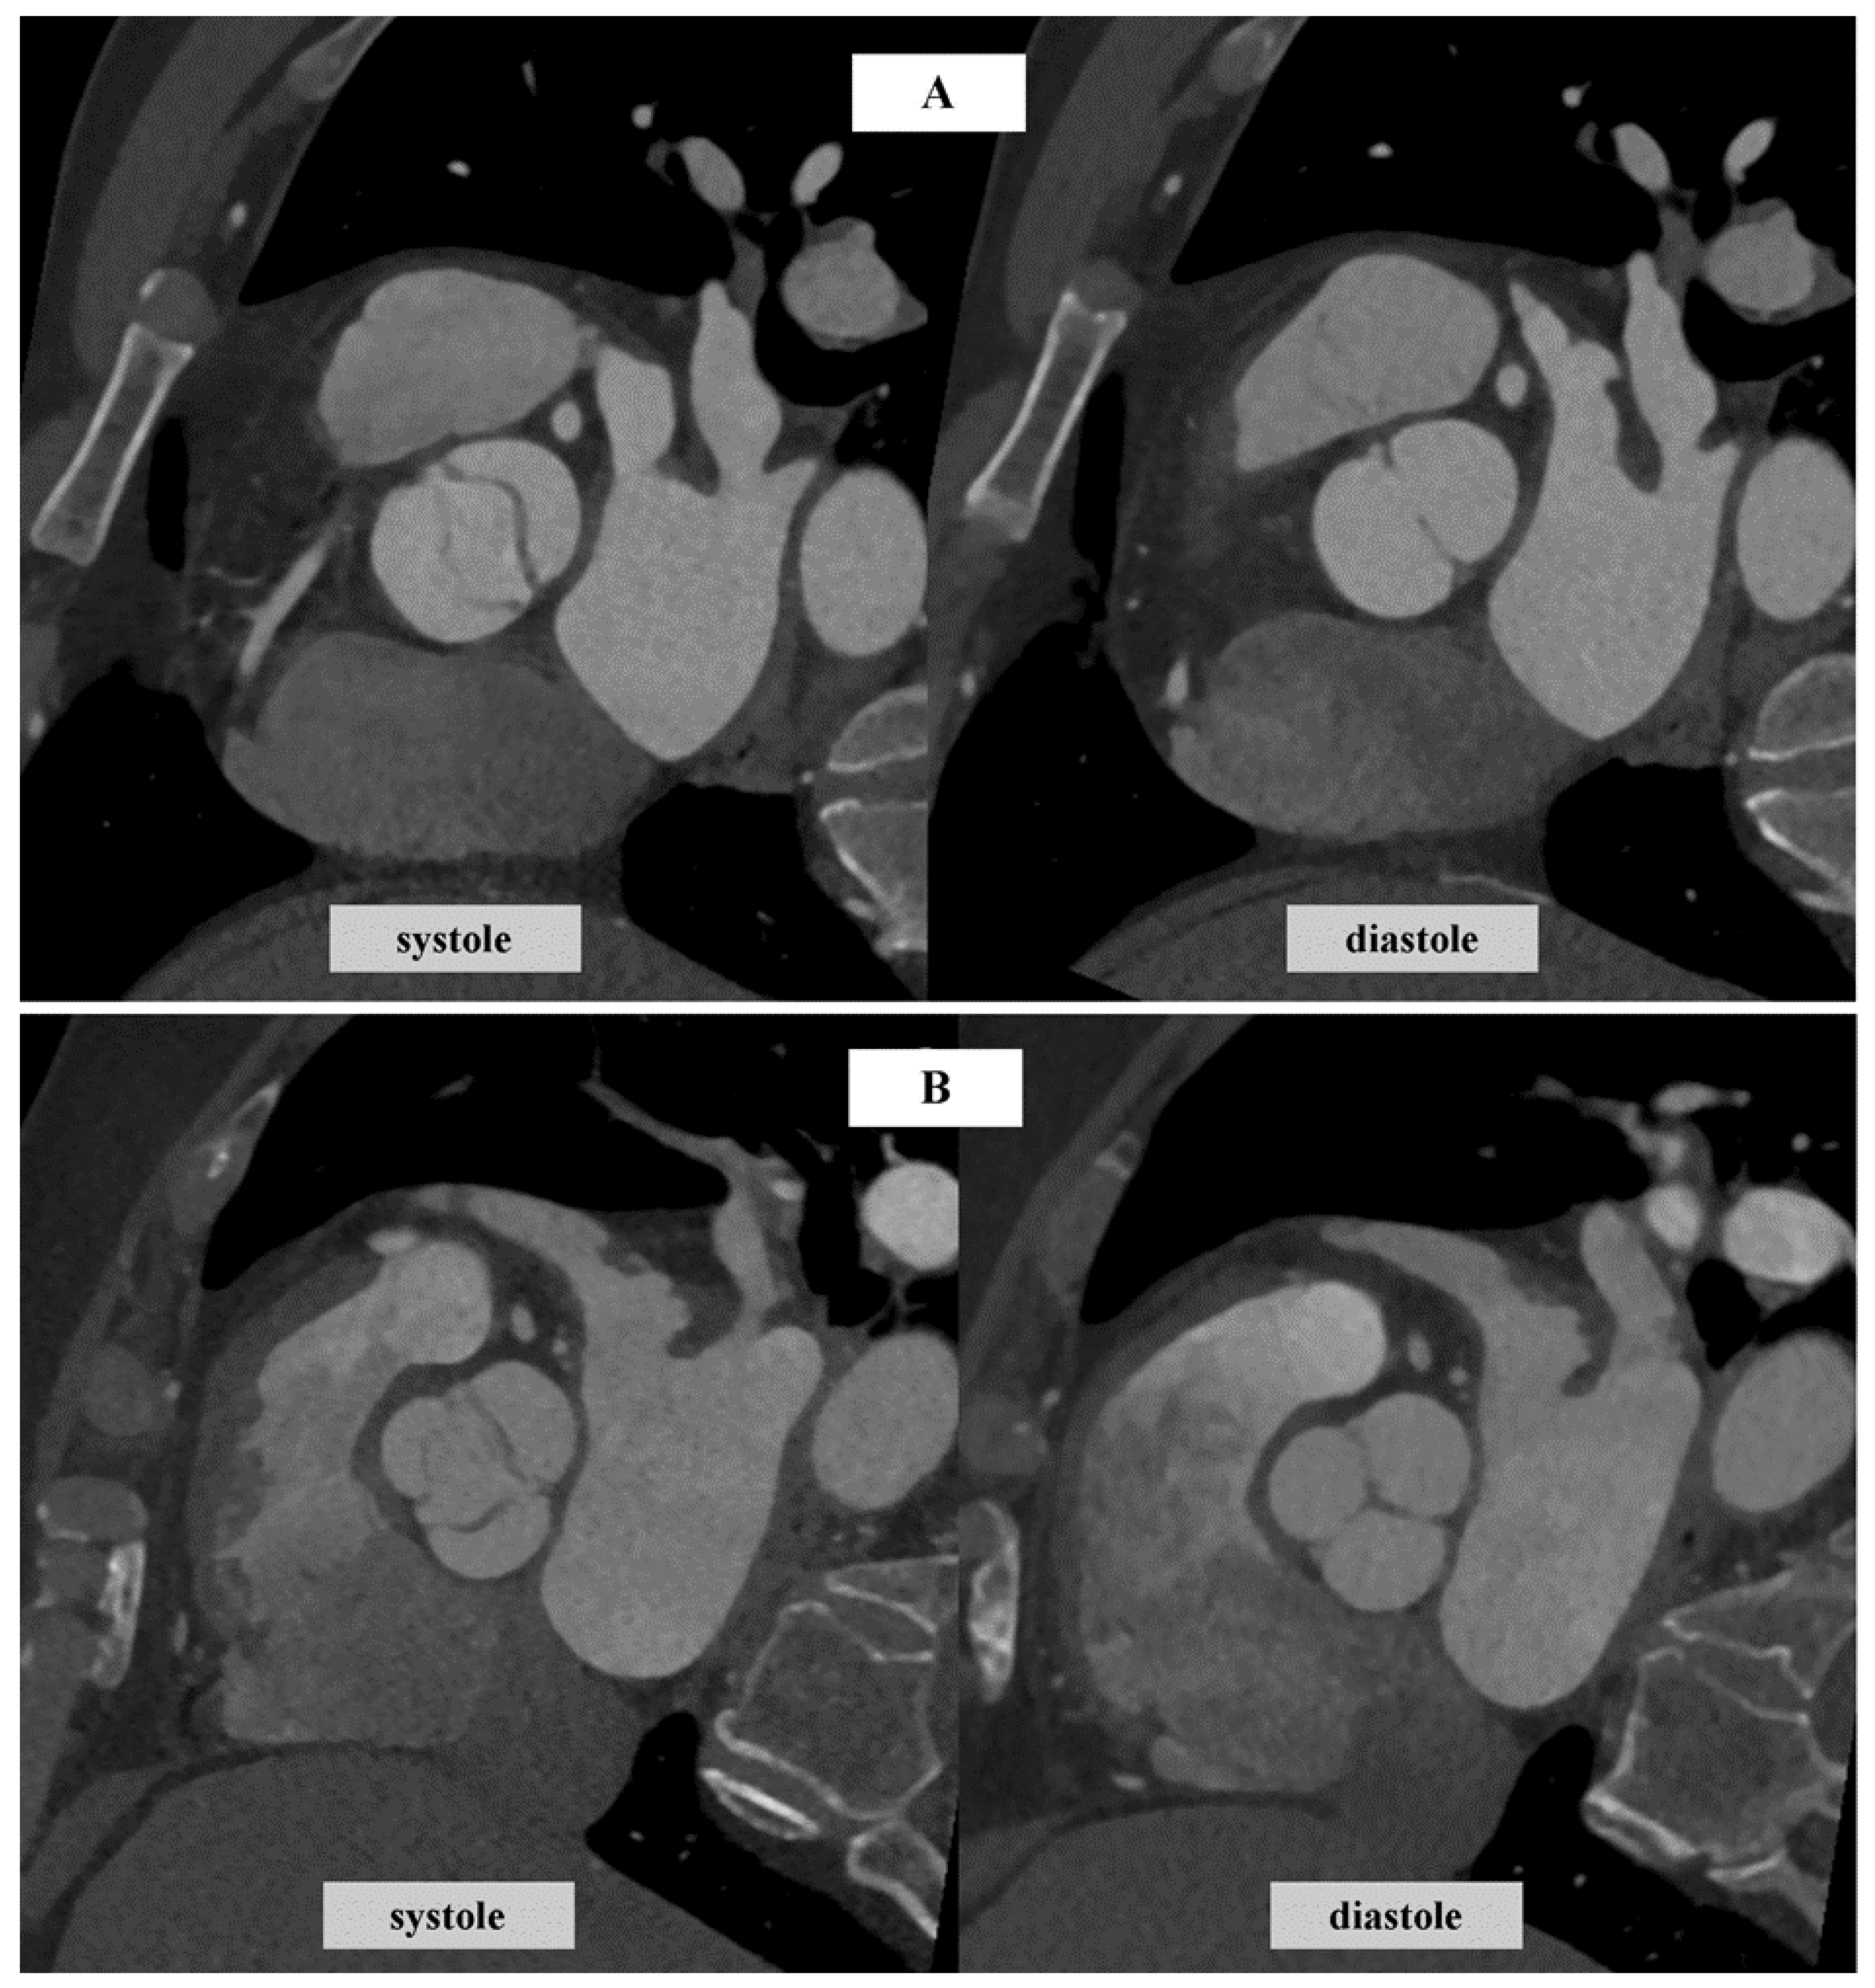

- Gać, P.; Kędzierski, B.; Macek, P.; Pawlas, K.; Poręba, R. Estimation of Aortic Valve Calcium Score Based on Angiographic Phase Versus Reduction of Ionizing Radiation Dose in Computed Tomography. Life 2021, 11, 604. [Google Scholar] [CrossRef] [PubMed]